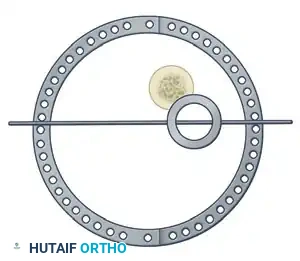

The management of complex, comminuted, or open tibial shaft fractures presents a formidable challenge to the orthopedic surgeon. The Ilizarov external fixation system, pioneered by Professor Gavriil Ilizarov, revolutionized the treatment of these injuries by introducing the concept of the tension-stress effect. Unlike rigid internal fixation, the Ilizarov circular frame utilizes tensioned fine wires to provide exceptional shear and torsional stability while permitting controlled axial micromotion. This unique biomechanical environment stimulates robust secondary bone healing (callus formation) without the need for extensive soft tissue stripping at the fracture site.

The efficacy of the Ilizarov frame relies on the precise geometric arrangement of rings and tensioned wires. Standard fine wires (1.5 mm to 1.8 mm) are tensioned to 110–130 kg, transforming them from flexible filaments into rigid beams capable of supporting physiological loads.

Step 2: Reference Wire Placement and Frame Suspension

To establish the foundational alignment of the construct, proximal and distal reference wires must be placed accurately.

- Hold the frame in the desired position and insert proximal and distal transverse reference wires. These wires must be placed parallel to the knee joint line (proximal) and the ankle joint line (distal).

- Frame Attachment: Attach the wires to the rings without bending them to meet the frame. Bending wires introduces asymmetric tension and weakens the construct. If a wire does not sit flush against the ring, use small washers or spacers to build the connecting bolts off the frame to meet the wire in its natural trajectory.